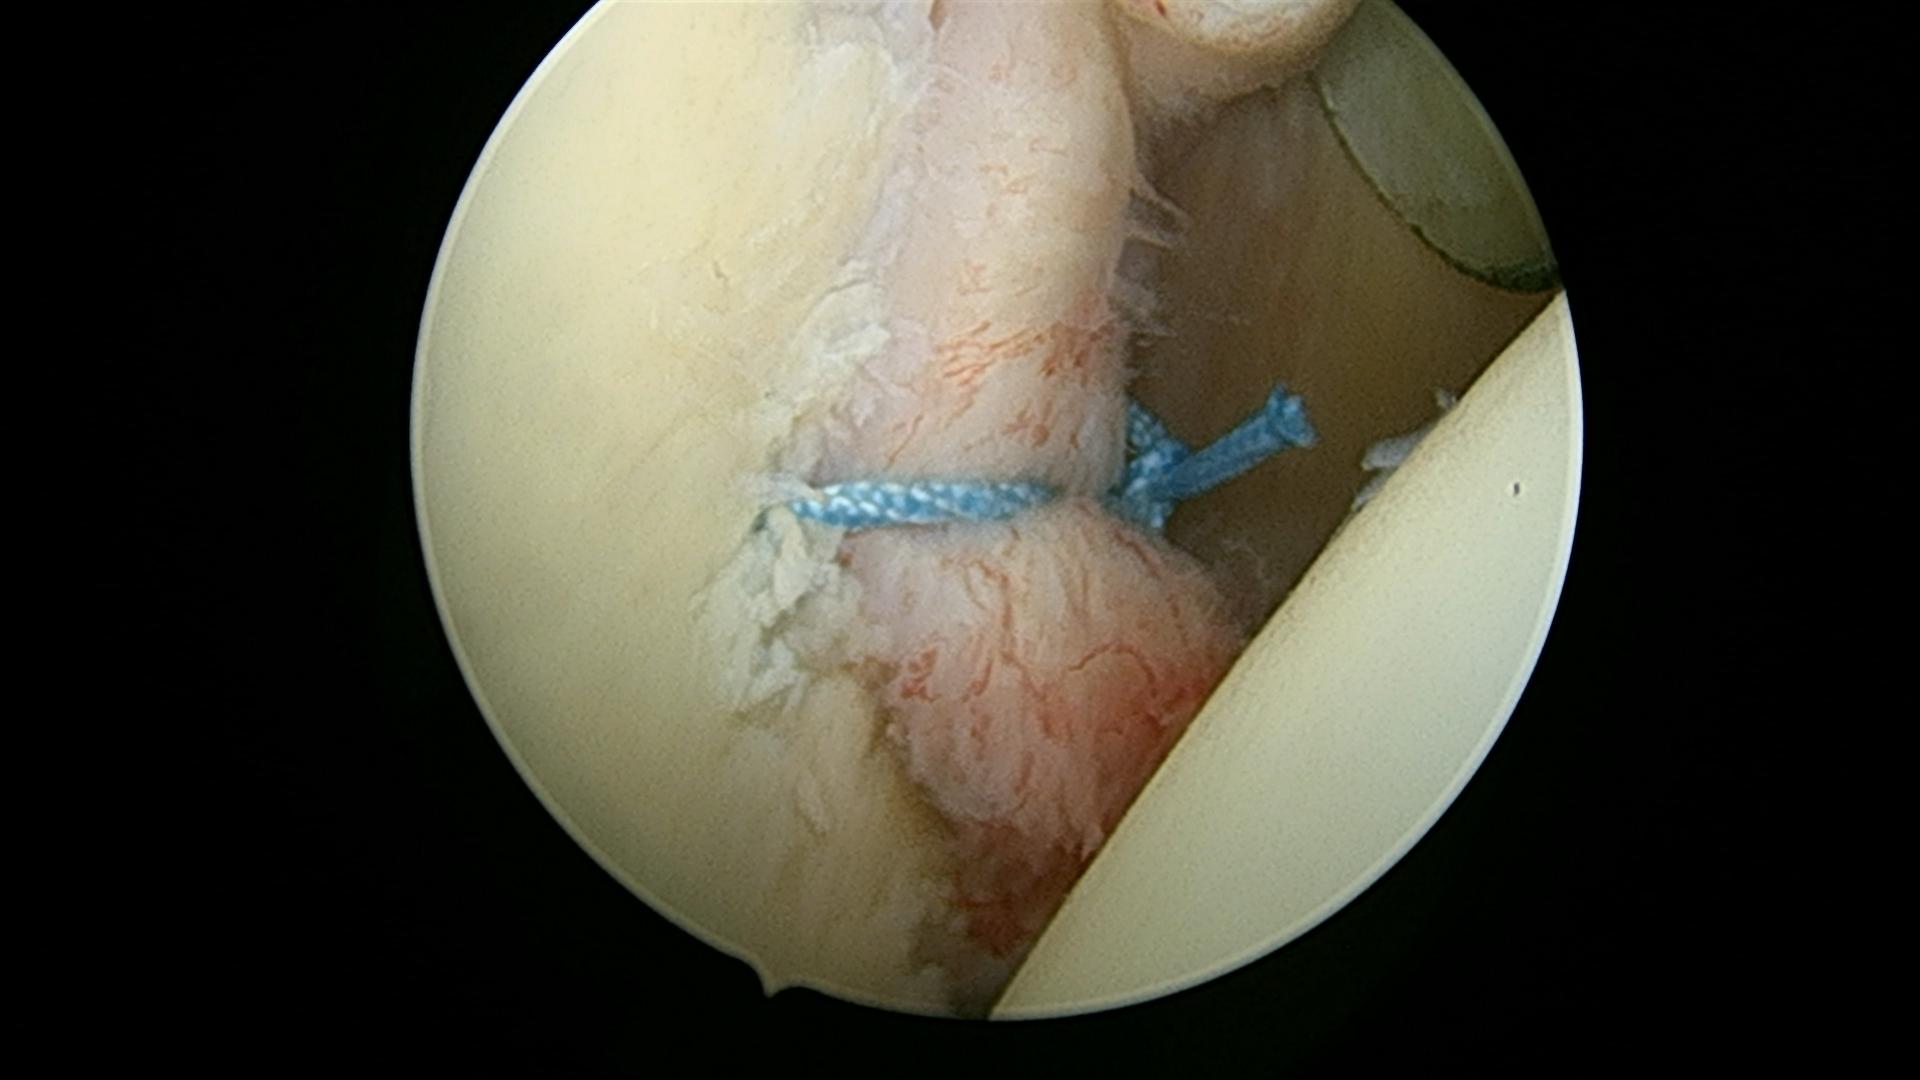

Efter refiksation: